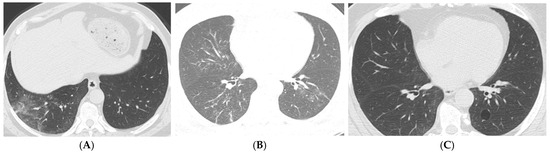

| Cyst | 0 (0%) | 0 (0%) | 0 (0%) | 0 (0%) | 3 (21%) | 1 (5%) | 0.007 |

| Imaging Findings (>12 Months) | Common Findings | Persistent fibrotic changes, cysts, ground-glass opacities |